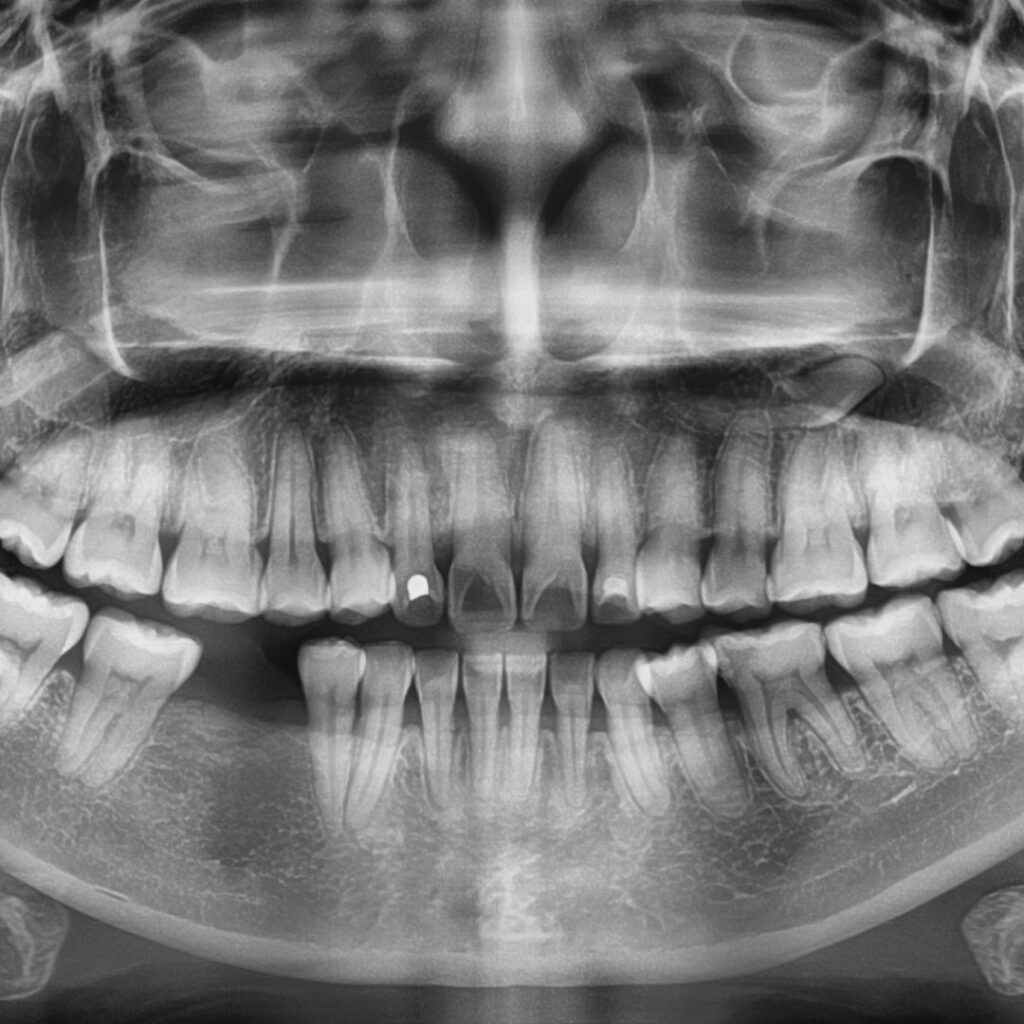

2. CT a rentgeny přímo v zubní ordinaci – pro diagnózu bez hádání

Díky CBCT pořídíme všechny potřebné rentgeny rovnou u nás v ordinaci – nebudete tedy muset odkládat léčbu, ani chodit jinam pro pořízení potřebných snímků.

Tyto informace umožní týmu co nejpřesněji stanovit diagnózu a provést léčbu bez hádání příčiny.

Výše zmíněné 3D rentgeny (CT skeny) jsou navíc zásadní pro plánování implantátů. Díky těmto informacím vytvoříme léčebné plány a zubní náhrady, které vám budou sloužit roky.